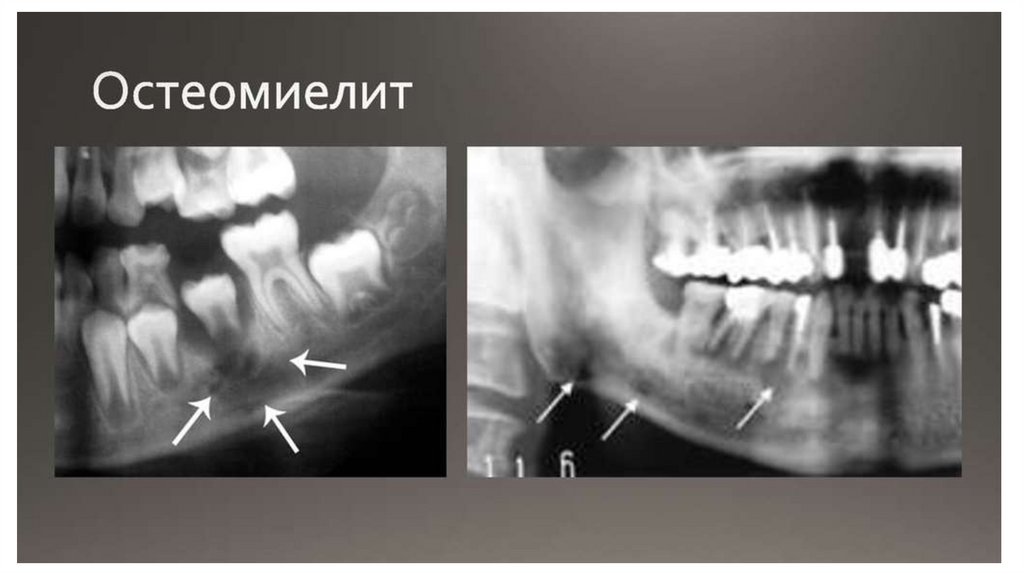

НО! Причина

нозокомиальных

пневмоний,

сепсиса, абсцесса,

остеомиелита итд